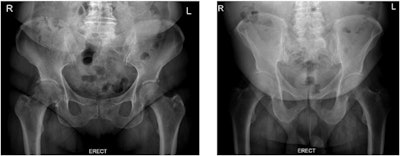

To address these challenges, the group tested whether radiation dose and image quality differ between two different erect pelvic radiographic procedures -- those with and without the displacement of anterior adipose tissue.

The radiographer who performed the exams properly positioned a thin cotton triangular bandage around patients, which they then held. Prior to the clinical study, the researchers had tested the material on an anthropomorphic phantom to ensure it would not be visible as an artifact.

In the group of patients using the fat displacement protocol, a statistically significant reduction in waist circumference (4.7%), dose area product (38.5%), entrance surface dose (44%), and effective dose (38.7%) were observed (p < 0.05), according to the findings.

"Image quality was generally better when patients had fat tissue displaced from the region of interest, as body part thickness decreased, resulting in improved contrast resolution and lower noise levels," the group wrote.